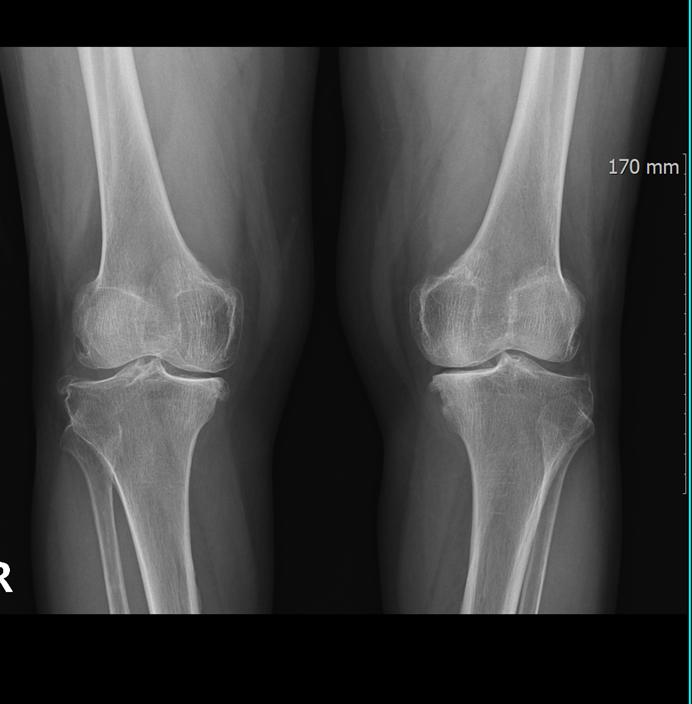

Knee Care

We offer comprehensive knee care, utilizing state-of-the-art imaging technologies. Our team specializes in diagnosing and treating various knee conditions, including arthritis and injuries, with both conservative and minimally invasive techniques designed to restore functionality and reduce pain, tailored to each patient’s needs.

Diagnostic Imaging

At MADI-BONE CLINIC, we provide comprehensive diagnostic imaging services, including X-ray, ultrasound, and C-arm technologies. Our advanced imaging facilities enable same-day diagnosis, allowing for swift treatment decisions and timely care for various orthopedic conditions, ensuring prompt and effective patient management.